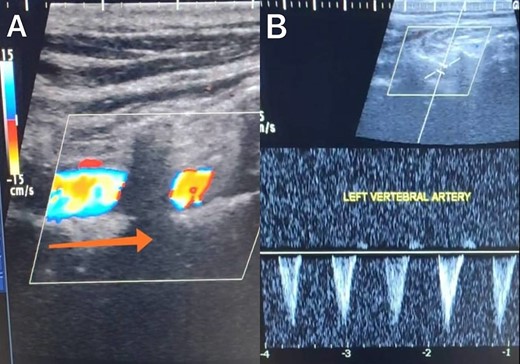

A 65-year-old male presented with recurrent transient ischemic attacks (TIAs), characterized by severe balance disturbances, transient alterations in consciousness, and visual obscurations. Clinical examination revealed high blood pressure in the right arm and absent left radial and brachial artery pulses. Vital signs were normal. Laboratory tests are analyzed as follows: urea: 22 mg/dl, glucose: 150 mg/dl, cholesterol: 199 mg/dl, and triglycerides: 222 mg/dl. A medical history of type 2 diabetes mellitus (DT2), hypertension (HTN), hyperlipidemia, ischemic heart disease, and a heavy smoking history were recorded. Five years before presentation, the patient underwent coronary stenting. Medication history included metformin 1000 mg, aspirin 81 mg, rosuvastatin 40 mg, and ramipril 5 mg. Neck duplex ultrasound (DU) showed normal flow direction and insignificant atherosclerotic plaques in the left internal carotid artery (CA) and left external CA (Figs 1 and 2), normal common CA (Fig. 3), a completely inverted flow direction in the left VA (Fig. 4) that suspected a significant ostial lesion in the left SCA. Multi-slice computed tomography angiography demonstrated 99% stenosis at the left SCA origin and confirmed the presence of SSS (Fig. 5). A balloon angioplasty was unsuccessfully attempted to expand the left SCA. A left carotid VA bypass surgery was performed, and a vascular graft was used to establish a blood flow pathway between the left VA and the left CA. By follow-up, the patient was stable without complications.

Duplex ultrasound showing a normal flow direction and insignifcant atherosclerotic plaques in the left external carotid artery.